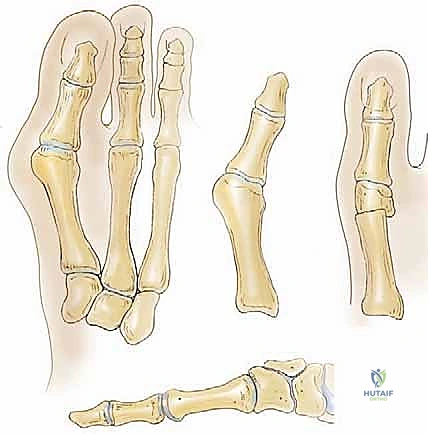

- استئصال البروز العظمي (Bunionectomy): يتم إزالة الجزء البارز من العظم (الوكعة) بعناية فائقة.

- تحرير الأنسجة الرخوة (Soft Tissue Release): هذه خطوة حاسمة. يتم تحرير الأربطة المشدودة من الجانب الخارجي للمفصل (مثل وتر العضلة المقربة)، مما يسمح للإصبع بالعودة إلى وضعه المستقيم دون شد.

- القطع العظمي المتدرج (The Mitchell Osteotomy): باستخدام مناشير جراحية دقيقة جداً (Microsurgery tools)، يقوم الدكتور هطيف بعمل قطع عظمي مزدوج (على شكل درجة سلم) في عنق المشط الأول. يتم ترك جسر عظمي صغير لضمان الاستقرار.

- إعادة المحاذاة والإزاحة: يتم إزاحة رأس المشط الأول نحو الخارج (باتجاه المشط الثاني) لتصحيح الزاوية، ويتم توجيهه قليلاً للأسفل.

- التثبيت الداخلي (Internal Fixation): لتأمين العظم في وضعه الجديد حتى يلتئم، يتم استخدام تقنيات تثبيت حديثة. غالباً ما يستخدم الدكتور هطيف مسامير معدنية دقيقة (Screws) أو أسلاك كيرشنر (K-wires) التي لا تتعارض مع النمو.

- شد المحفظة المفصلية (Capsulorrhaphy): يتم خياطة وشد محفظة المفصل من الجانب الداخلي للحفاظ على التصحيح بقوة.